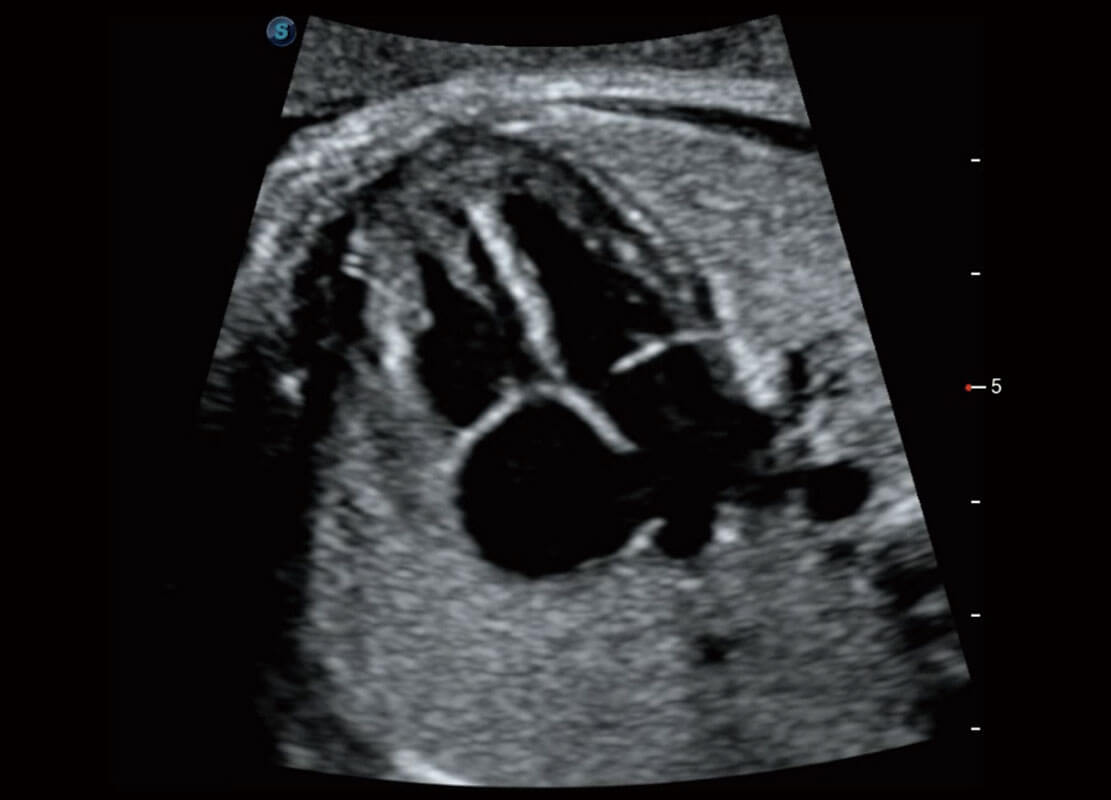

早孕-胎心

高分辨率容积成像-早孕胎儿

胎儿体循环

光影成像-孕囊